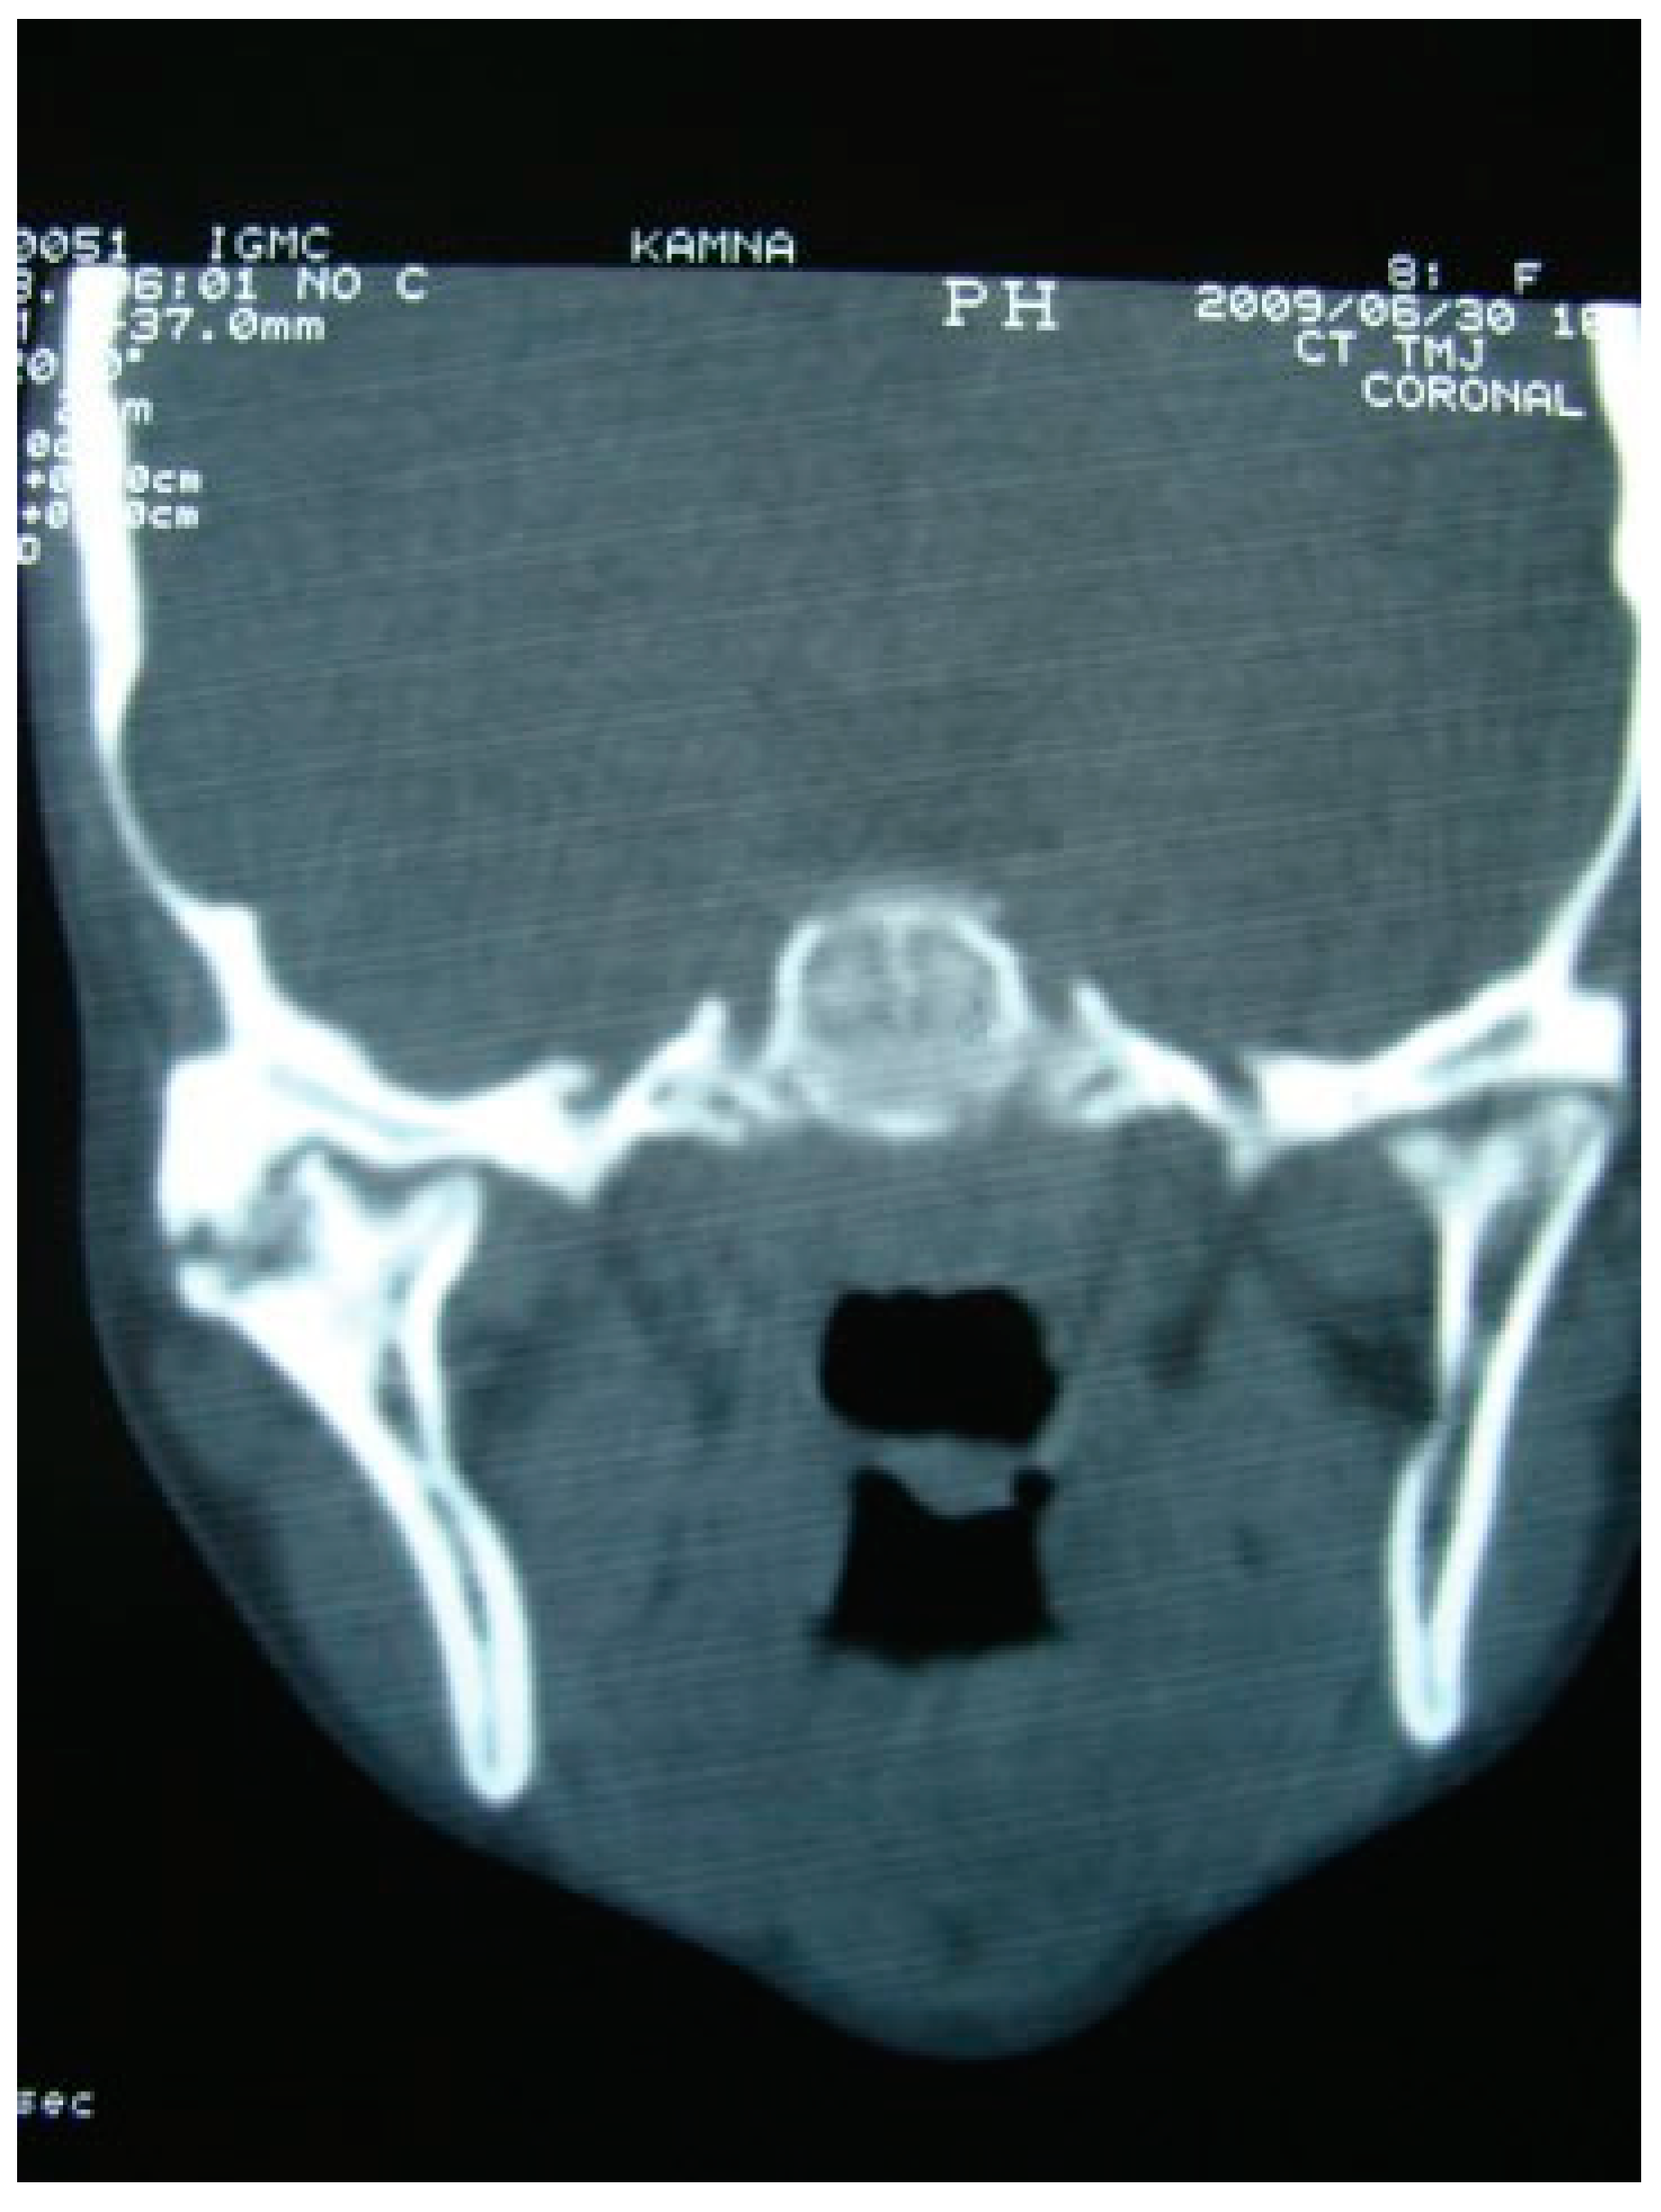

Figure 3. Preoperative coronal CT scan of right temporomandibular joint ankylosis.

A retrospective study of post–ankylotic TMJ reconstruction of all the patients who underwent surgery for the TMJ ankylosis over a period of 11 years from 2002 to 2013, which were operated by the senior author (Y.B.), was undertaken to evaluate demographics, type of TMJ ankylosis, and modality of post–ankylotic TMJ reconstruction. The following inclusion criteria were considered for enrolling patients in this study: (1) history of traumatic injury to the face or jaws; (2) clinical and radiographic evidence of bony ankylosis at the time of presentation; (3) reconstruction of the TMJ using autogenous or alloplastic material after surgical release of ankylosis. Patients were assessed for (1) maximum interincisal opening pre and post operatively; (2) restored vertical ramal height; (3) occlusion; (4) facial symmetry; and (5) postoperative complications. Radiographic evaluation consisted of both preoperative and postoperative panoramic radiography Orthopentomogram (OPG) (Figure 1 and Figure 2) and CT scans in axial, coronal, and sagittal sections with three-dimensional reconstruction (Figure 3 and Figure 4). Surgical protocol was that the TMJ was approached through the Al-Kayat and Bramley’s incision and at least 2 to 2.5 cm resection of the ankylotic chunk was performed in all our cases. Ipsilateral and contralateral coronoidectomy was performed when required to achieve passive mouth opening. Interpositional arthroplasty was done using various materials such as temporalis fascia, temporalis muscle, and articular disc, whereas joint reconstruction was done using CCG and titanium reconstruction plate with condylar head. Intensive physiotherapy postoperatively was an integral part of protocol.

He et al devised a new classification of TMJ ankylosis which was a modification of Sawhney’s classification based on the coronal CT scan and based their treatment protocol accordingly. Type A1 is fibrous ankylosis, where post release of fibrous tissue, joint reconstruction was done using temporalis myofascial flap (TMF), masseter muscle flap (MMF), or CCG. Type A2 is ankylosis with bony fusion on the lateral side of the joint, while the residual condylar fragment is bigger than 0.5 of the condylar head in the medial side, and type A3 is similar to A2 but the residual condylar fragment is smaller than 0.5 of the condylar head. In both A2 and A3, lateral arthroplasty was done and reconstruction was done using CCG, TMF, or MMF. In type A4, there is complete bony fusion and reconstruction was done using CCG, TMF, or MMF [9].